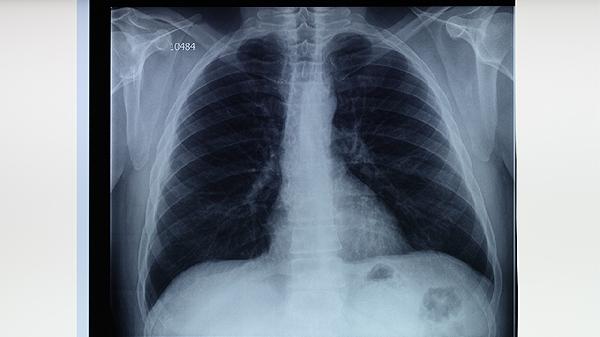

5. 病灶评估

胸部CT可发现X线难以显示的微小空洞病灶,指导延长强化期治疗。纤维支气管镜检查能获取支气管内膜结核标本,局部灌注异烟肼注射液可提高疗效。对持续排菌患者可考虑介入治疗或手术切除病灶。